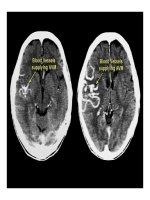

Tai biến mạch máu não gồm hai loại chính là nhồi máu não và xuất huyết não. Nhồi

máu não xảy ra do tắc động mạch nuôi vì nhiều nguyên nhân nhưng nguyên nhân

thường gặp nhất là huyết khối động mạch.